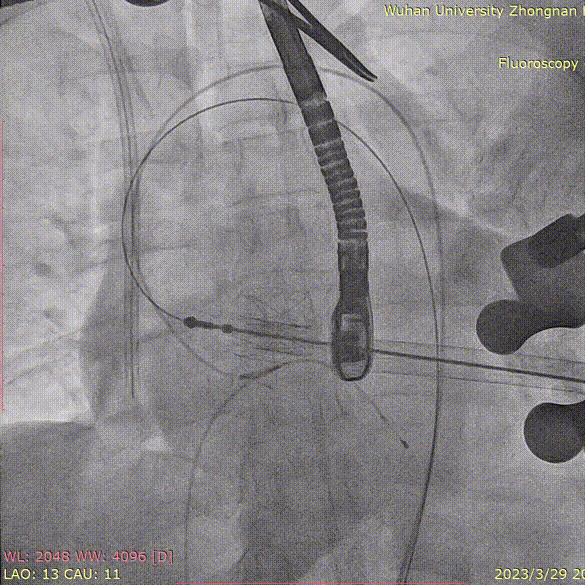

退出介入器:

血管减影造影,瓣膜形态正常、未见瓣周漏: